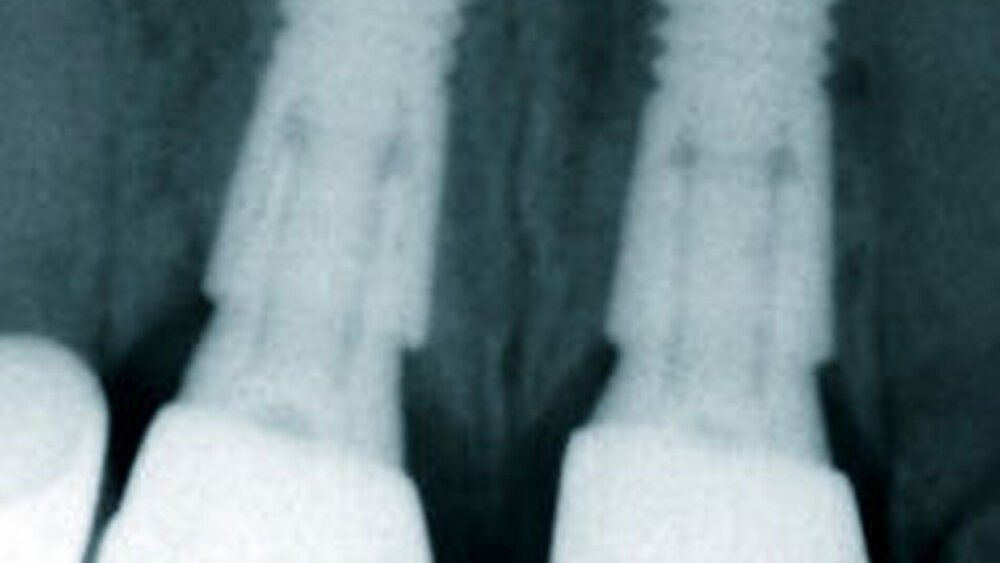

Bei einer jungen zahnlosen Patientin mit schmalem Alveolarkamm wurde klassisch präimplantologisch augmentiert (vestibulärer Knochenblock und BioOss-Anlagerung, Bio- Gide-Membran-Abdeckung) mit vier bis sechs Monaten Einheilzeit. ‧Unglücklicherweise entwickelte sie eine Wunddehiszenz mit ausbleibender Knochenregeneration und Verlust des Augmentats. Eine erneute Augmentation kam für sie wegen der OP-Belastung und einer sich weiter verlängernden Therapiedauer nicht infrage. Als eine mögliche alternative Versorgung stimmte sie der Insertion von drei Profile EV-Implantaten mit abgeschrägter Implantatschulter zu. Die Kontrolluntersuchungen nach zwei und fünf Jahren zeigten eine sehr gute Osseointegration und zudem eine sehr gute stabile periimplantäre Weichgewebssituation ohne zusätzliche peri‧implantäre Weichgewebsver‧dickung, ein Phänomen, so Wagner, das ein typischer Weichgewebevorteil für alle Implantate mit Platform Shift sei, nicht nur für das Profile EV. Als Hauptindikationen für diese anatomischen Implantatformen nannte Wagner

Dass sich Implantate mit abgeschrägter Schulter im Praxisalltag bewähren, belegt eine aktuelle Feldstudie mit Beteiligung von mehr als 20 niedergelassenen Kollegen [1]. Wagner: „Wir haben als Gruppe mehr als 200 TXProfile-Implantate gesetzt, nur zwei gingen verloren. Das ist ein extrem gutes Ergebnis.“ Zudem habe das Profile-Implantat einen beachtlichen positiven Einfluss auf das Weichgewebe, was aber nicht nur auf die Implantatgeometrie, sondern auch auf den Platform Shift zurückzuführen sei. „Rund 40 Prozent der Implantate von Dentsply Sirona Implants, die wir im Unterkieferseitenbereich und der Oberkieferfront setzen, sind inzwischen Profile-Implantate des Astra Tech Implant-Systems.